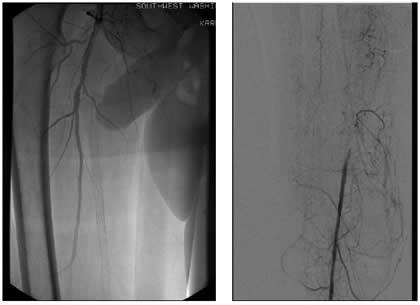

Case 3: An 81-year-old male with rest pain. The patient underwent angiography via an antegrade approach, which revealed extensive

| Figure 3C |

calcific lesions of the superficial femoral artery (Figure 3A) and a lesion in the tibio-peroneal trunk (Figure 3B). The SFA lesions were debulked with a laser and the patency restored with Viabahn stents (Figure 3C). The tibio-peroneal represented the sole run off and was left as we were worried about creating a disaster if the lesion ruptured or dissected. ABI increase from 0.19 pre-procedure to 0.55 post and the patient is now able to ambulate with manageable claudication. Options to treat the more distal lesion could involve using a distal protection device and coronary balloons and/or stents.